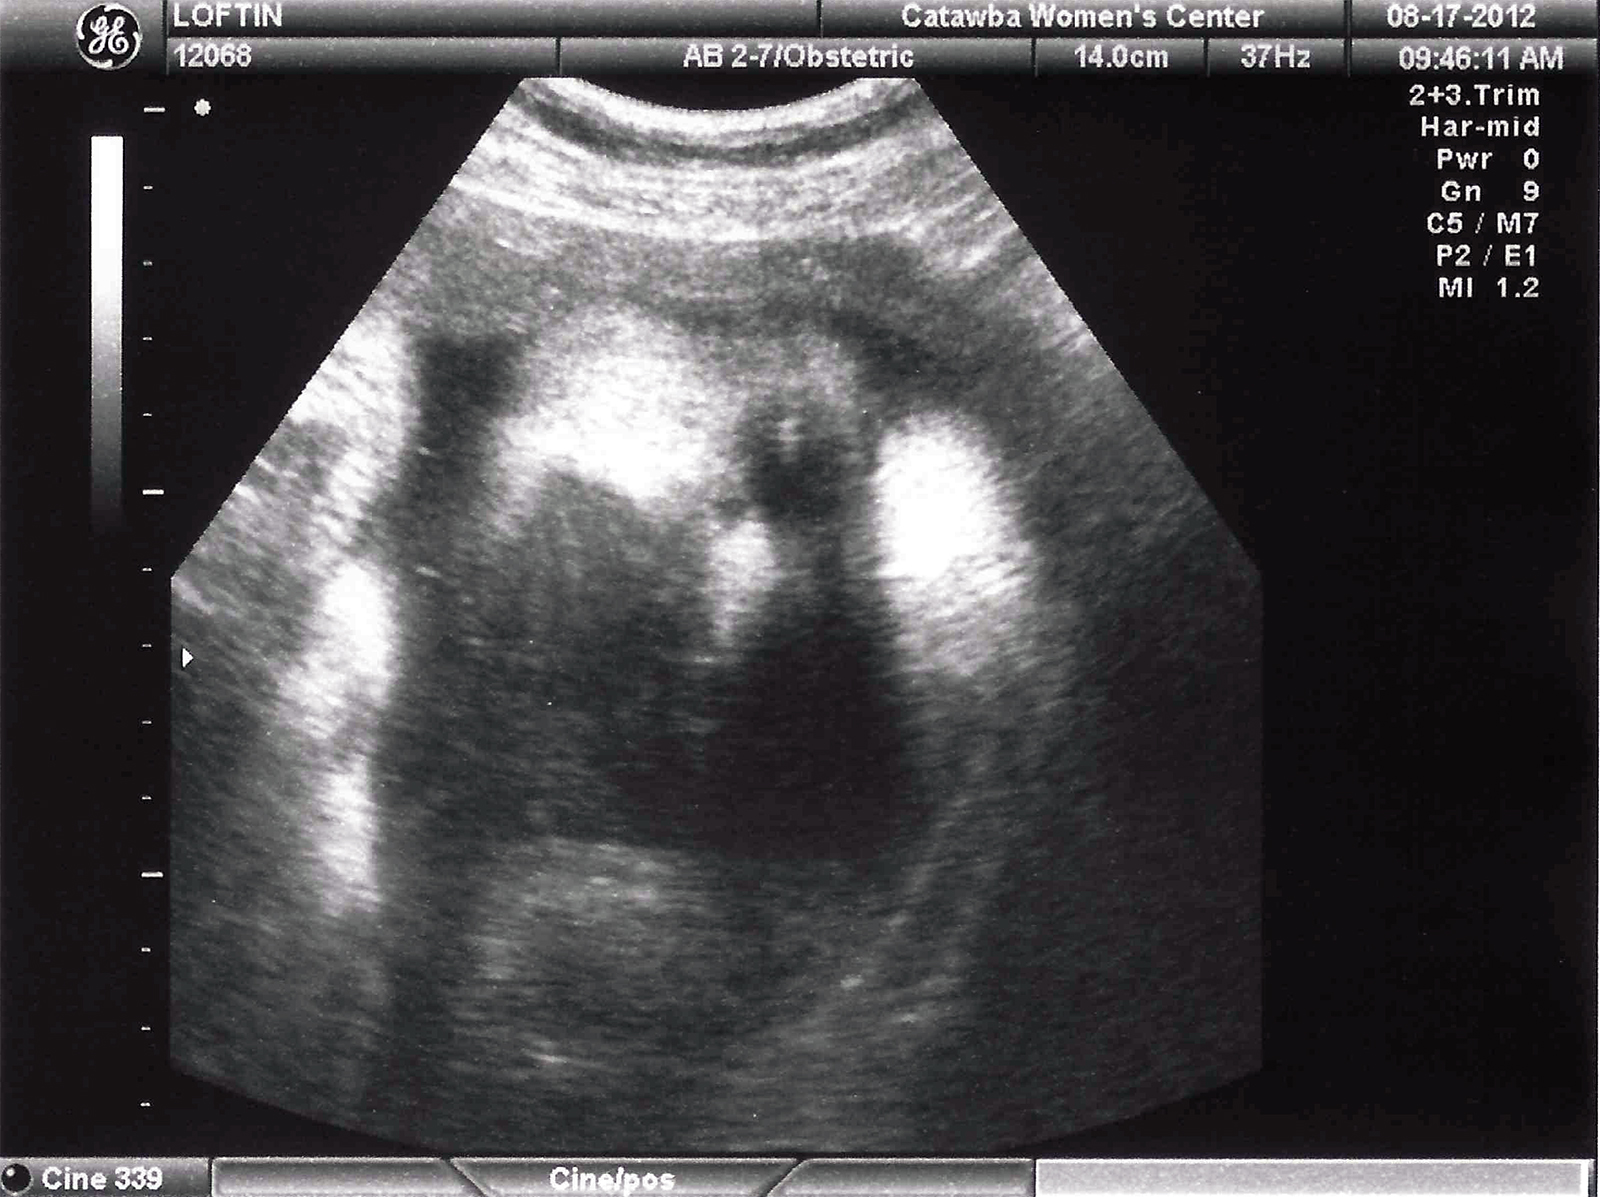

by: Philip LoftinPosted on: August 17, 2012November 23, 2014 Ultrasound (37 weeks) Below are ultrasound pictures from Aug 17, 2012. This visit, Kayli is estimated to be 7 pounds 14 ounces. Taken at 37 weeks